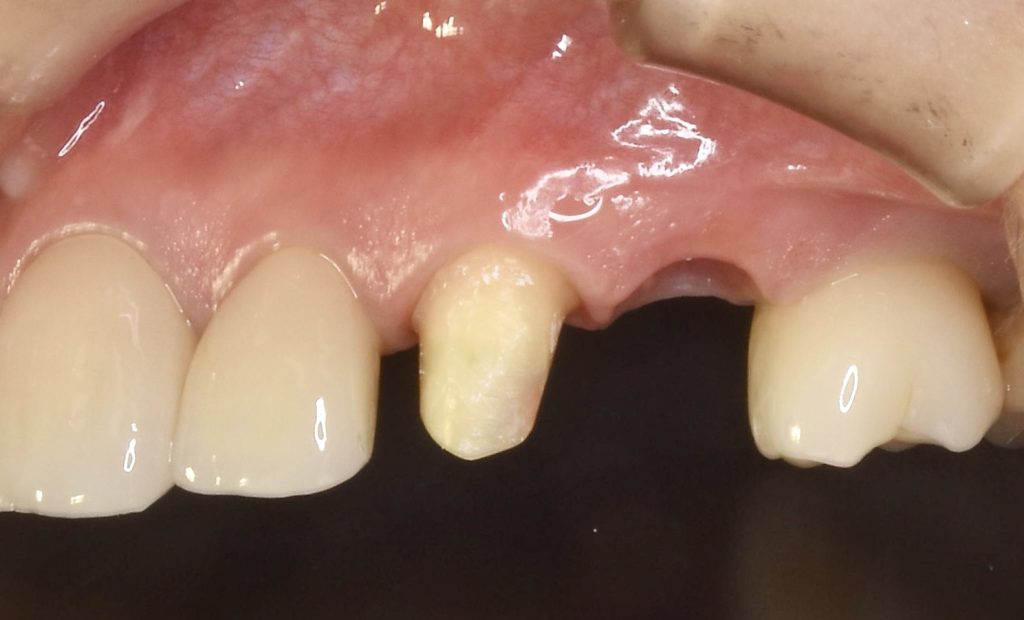

下記の症例は当院の審美領域のインプラント治療の治療結果となります。

治療後、どの歯を抜歯してインプラント治療を行ったか見分けがつかないような治療結果に拘っています。

治療後のクオリティーはもちろん、できるだけ負担の少ない術式を意識し、患者ファーストを第一に考えております。

この症例に発生する費用 約85万円(税抜)